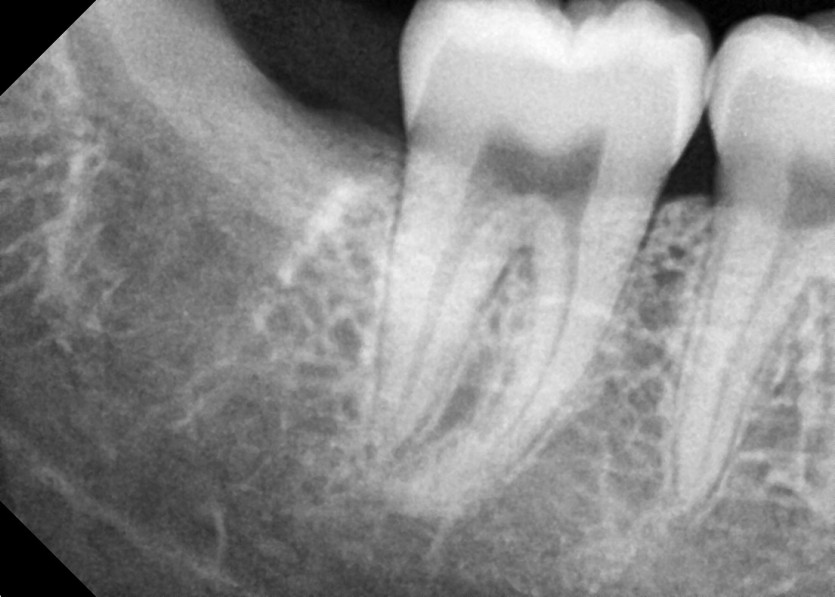

#48 사랑니 발치

구강 외과 전문의가 당일 발치했습니다.